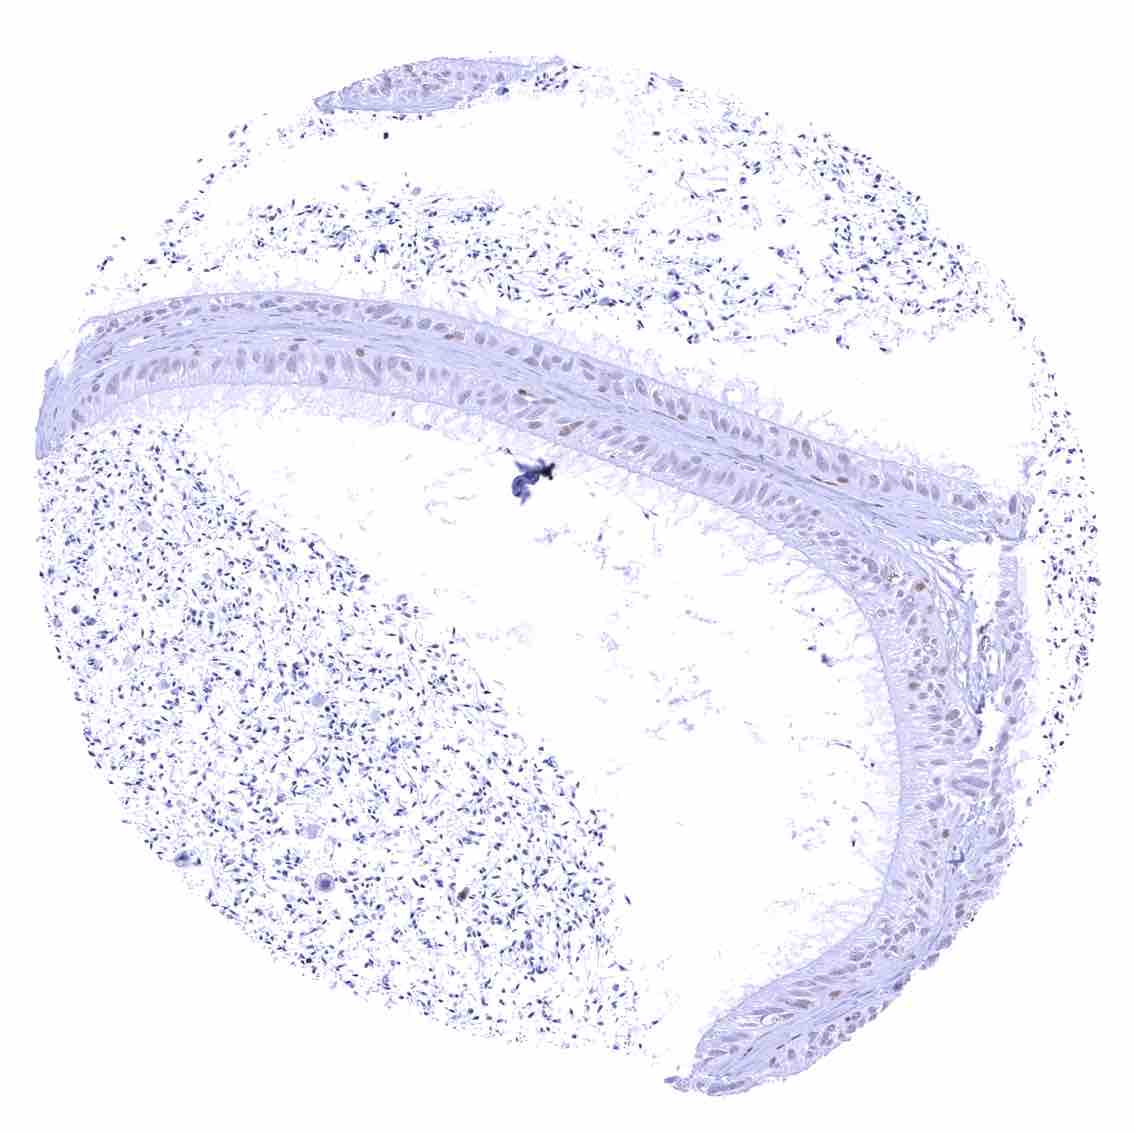

Uterus, ectocervix – Nuclear staining of squamous epithelial cells predominates in the more mature cell layers (top 50_ of the epidermis).